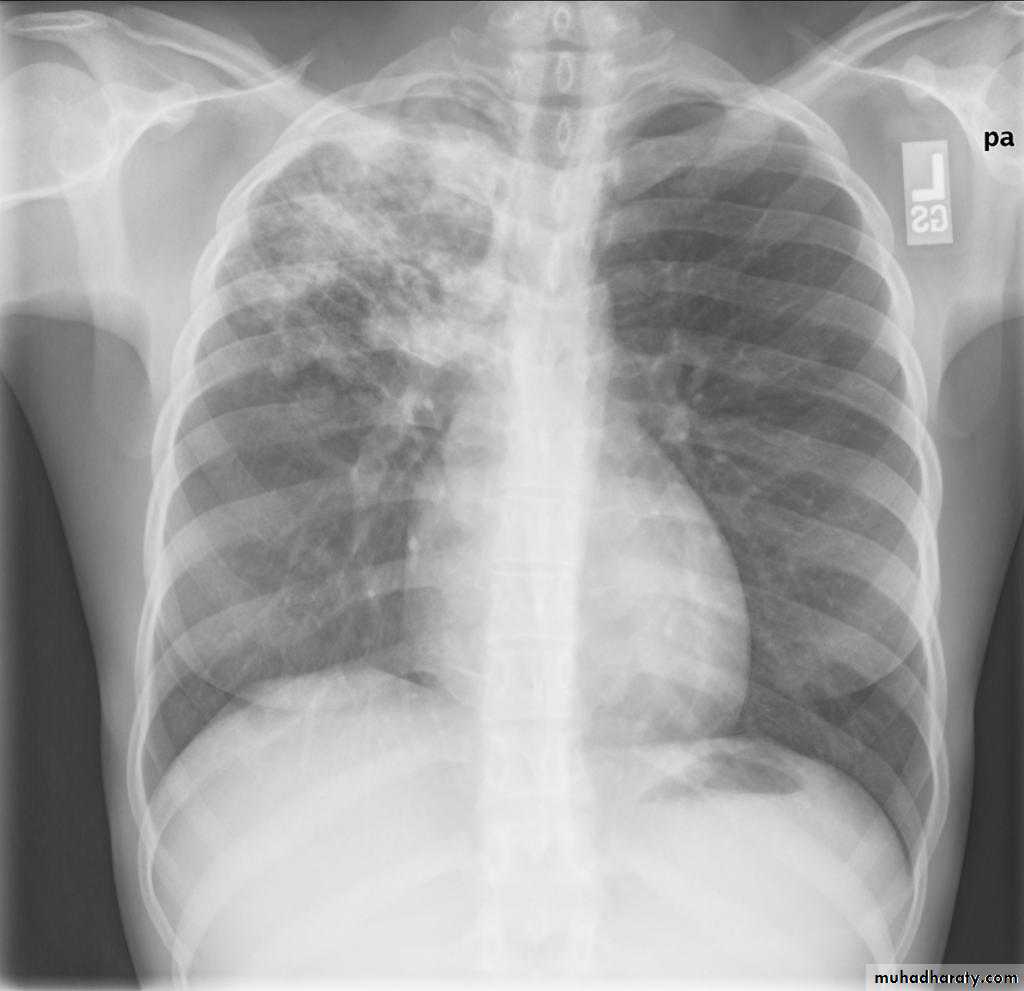

Plain filmExcept in the case of very advanced disease with bulla formation, chest radiography does not image emphysema directly, but rather infers the diagnosis due to associated features :

hyperinflation:

1.flattened hemidiaphragm(s): most reliable sign

2.ncreased and usually irregular radiolucency of the lungs

9.vascular changes paucity of blood vessels ( absent pulmonary markings in outer 1/3 of the lung fields )